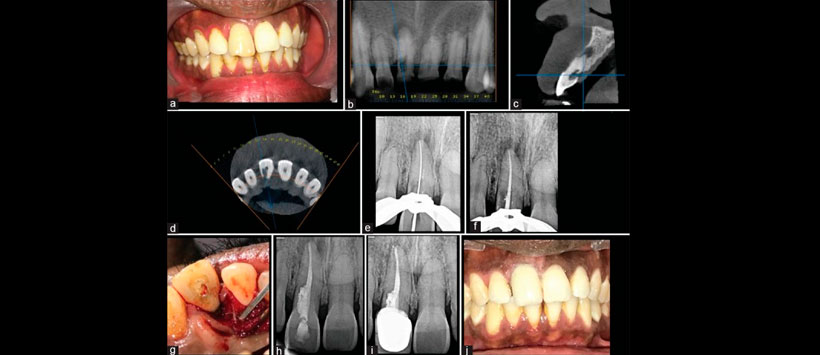

Biodentine puede demostrar ser un material particularmente adecuado para restaurar estos defectos porque puede combinar una estética aceptable con la capacidad de soportar la unión del ligamento periodontal (PDL). Los siguientes informes de casos describen el manejo quirúrgico de la resorción externa con la mejor opción de material restaurador de biodentina (ver figuras 1 y 2).

Figura 2: (a) Fotografía intraoral preoperatoria (vista bucal), (b) Análisis de tomografía computarizada de haz cónico en el plano coronal, (c) Análisis de tomografía computarizada de haz cónico en el plano sagital de la reabsorción cervical invasiva en la pieza 11, (d) Plano de haz cónica en el plano axial computada análisis tomográfico de la resorción cervical invasiva, (e) determinación de la longitud de trabajo (f) colocación del cono maestro, (g) reflexión del colgajo mucoperióstico, (h) radiografía posoperatoria inmediata, (i) seguimiento postoperatorio de 6 meses radiografía, (j) seguimiento postoperatorio a los 6 meses (vista bucal)